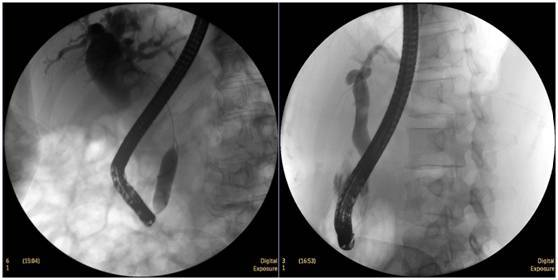

鼻膽管造影

立位注入造影劑,膽總管顯影好,稍擴張,未見結(jié)石影。